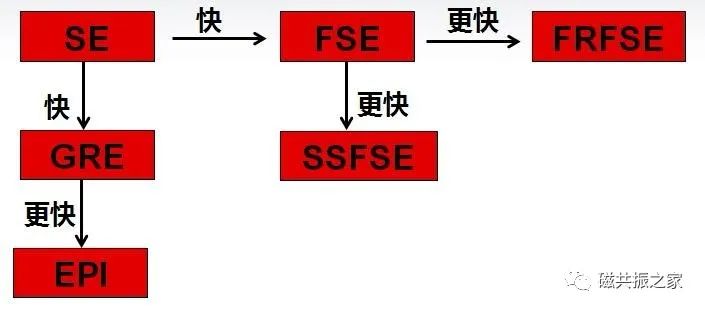

一、改变序列

SE序列:一个TR填充K空间一条相位编码线,每采集一次需等待TR长的时间再进行下一次激发,需要激发采集相位编码数次。

FSE序列:引入了回波链(如N),一个TR填充K空间的N条相位编码线,极大的缩短了扫描时间。

FRFSE序列:使用一个翻转恢复脉冲快速地将组织的磁化矢量由激发态恢复至平衡态,以达到加快扫描速度的效果。

SSFSE序列:一个TR时间内填充完K空间的全部相位编码线。通常采集相位编码矩阵一半多点的K空间线,再利用K空间的共轭属性重建另一半的数据。

GRE序列:与SE序列相比极大的缩短了TR,使用不同的TE及FA可得到多种权重的对比,使得快速成像成为可能。

EPI序列:EPI技术是在一次RF激发后,采用正反梯度连续切换来读取采集信号,极大的缩短了扫描速度。

EPI的序列是目前成像速度最快的序列,该序列不局限于DWI、PWI等成像,还可以结合不同的序列得到不同权重的图像。